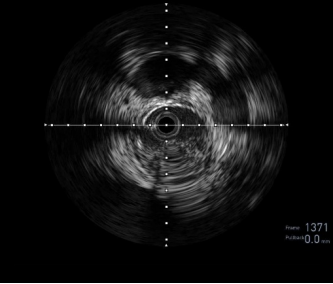

图:OA 基线造影

图:IVUS测量

图:Diamondback 360 减容

图:DCB扩张后 全程造影